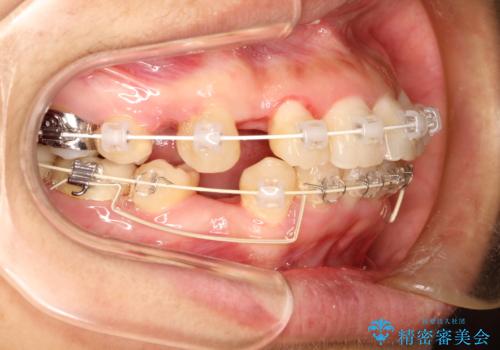

上下の歯のガタガタ ワイヤーでの抜歯矯正で整った歯並びへ

- 矯正装置

- 上下の歯のガタガタを治したいとのことで来院されました。

がたつきの度合いが強いのと、口元をなるべく引っ込めたい希望がありましたので、ワイヤーでの抜歯矯正となりました。

ガタガタが重度の方は抜歯が必要となることが多いです。

抜歯スペースを使って前歯を引っ込めることにより、口元の突出感も改善できました。